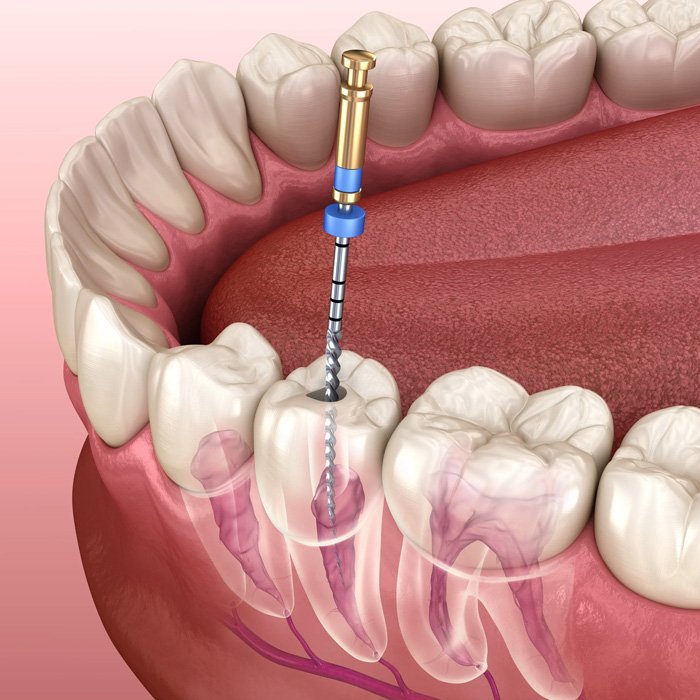

Experience Best in Dental Care

At Stellar Smiles Clinic, we believe a beautiful smile has the power to boost your confidence and enhance your overall well-being. Our expert dental team combines advanced technology with gentle care to give you an exceptional treatment experience. Whether you need a routine checkup or a specialized procedure, we ensure comfort, precision, and the highest level of safety at every step.